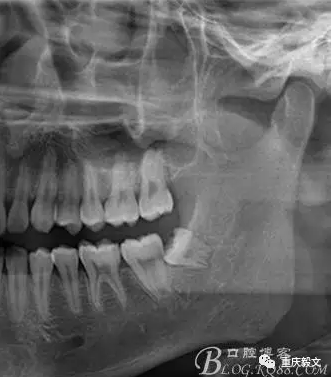

圖1 術(shù)前的影像檢查 : x線檢查的目的:檢查有無智齒的存在。如有阻生智齒存在,確定是部分骨阻生還是完全骨阻生。檢查阻生智齒的類型,是近中位、垂直位或水平位等。檢查阻生智齒的大小和牙根的長短、數(shù)目、形態(tài)等;有無牙根彎曲和彎曲方向與程度;牙根有無肥大、是否與周圍骨質(zhì)粘連。.檢查阻生智齒與第二磨牙的關(guān)系.檢查阻生智齒與下頜管的關(guān)系及距離.